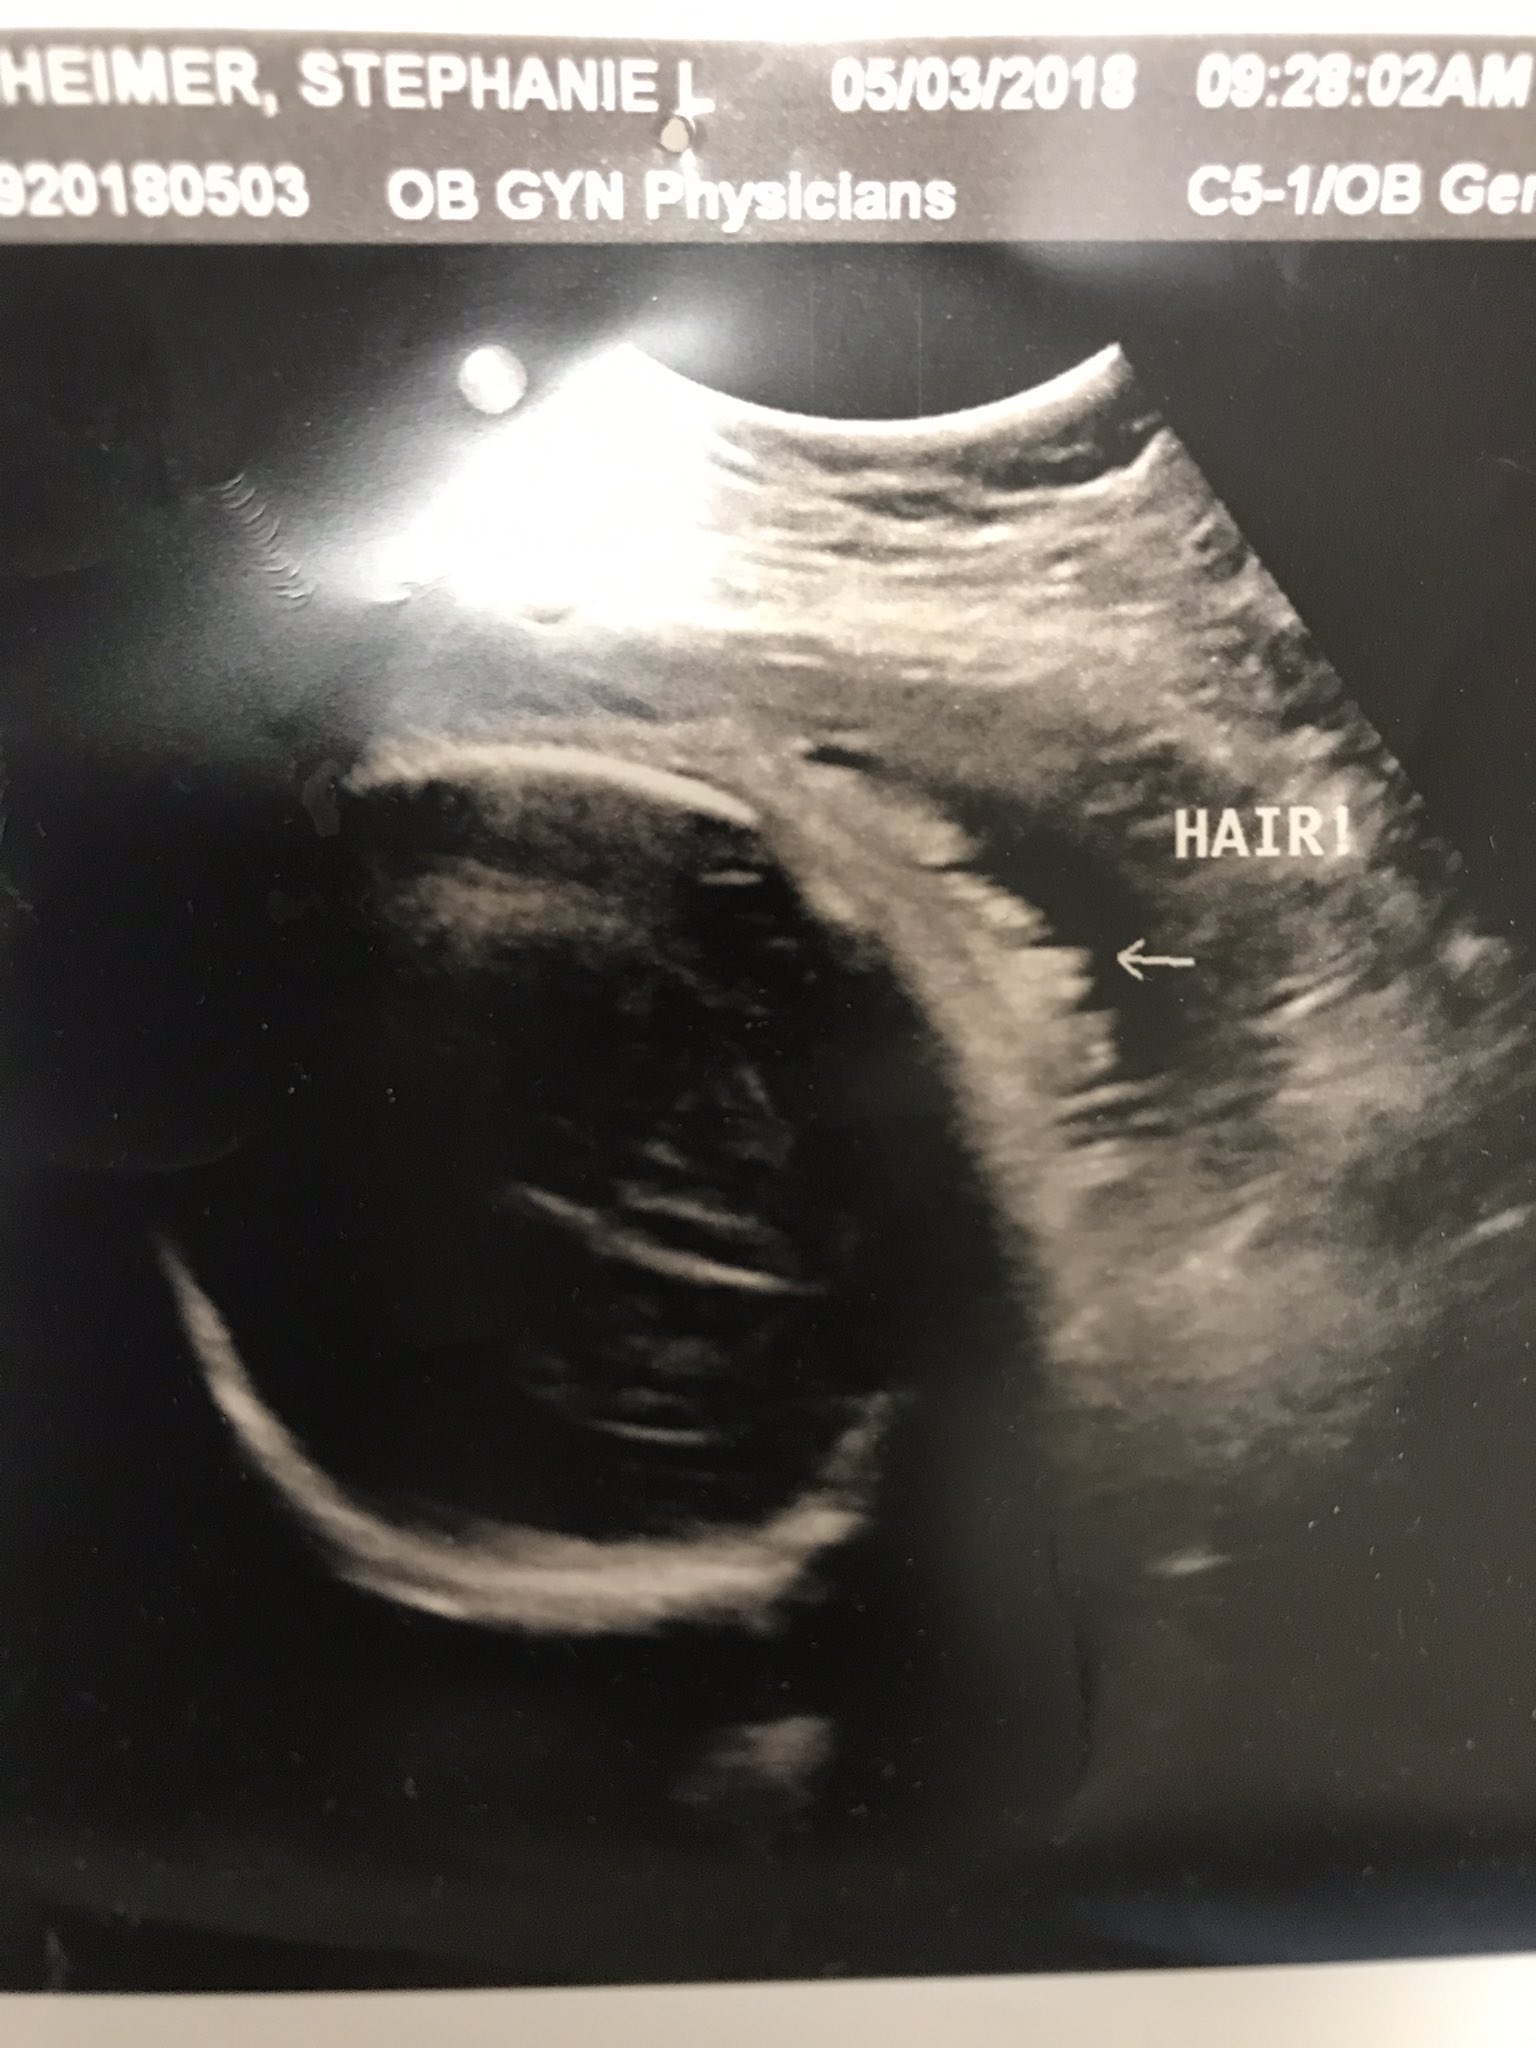

hair on ultrasound 32 weeks

I was so surprised that we could see it on a regular ultrasound. At our 32 week ultrasound we found.

Yes at our last ultrasound at like 32 weeks the tech commented that baby had a headful of hair. She said there was so much of it that it was floating around his head. Baby Hair On Ultrasound 32 Weeks.

She told me the little white lines on the head were hair. Unfortunately 3D4D ultrasound technology cannot see any hair on the baby however standard 2d black and white ultrasound can usually pick up strands of hair. He has a full head of blonde hair.

Yes - I could see little spikes of hair on the babys head at a 32 week growth check scan. Yes at our last ultrasound at like 32 weeks the tech commented. Unlike a traditional 2D Ultrasound a 3D Ultrasound allows you to see the width height and depth of the baby and sonographers and parents can also view babys.

Stephanie On Twitter This Is An Ultrasound Pic Of Miriam S Hair Taken 18 Days Before She Was Born Prolife Prolifegeneration Babies Babieslivesmatter Savethebabies Https T Co 7qmyk4kw6o Twitter

32 Week Ultrasound Showed That Our Son Has Hair R Predaddit